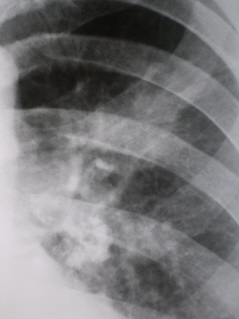

Иллюстрации 2, 3 – фрагменты рентгенограмм левого лёгкого в прямой проекции.

На томограммах – срезы 7, 9, 11 см. (прикрепленный файл) – иллюстрации 1 – 6 - слева в корне группа обызвествленных бронхо-пульмональных лимфатических узлов. Тень левого корня в области тела частично расширена, гомогенизирована. В средней легочной поле определяется фокусная тень не правильной формы, средней интенсивности, неоднородной структуры, с эксцентрически расположенным «просветлением», что указывает на «распад». От фокусной тени четко дифференцируются тяжи в сторону костальной плевры. Контуры не ровные, не четкие, по контуру определяются мелкие «спикулоподобные» структуры, что является свидетельством инфильтративного роста.

Заключение: Рак верхней доли левого лёгкого с локализацией в заднем сегменте. Пациент направлен в областной онкологический диспансер. Диагноз подтвержден.